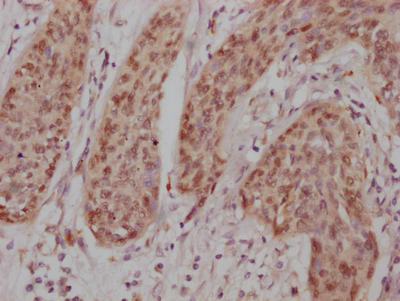

IHC image of CSB-RA911286A0HU diluted at 1:100 and staining in paraffin-embedded human cervical cancer performed on a Leica BondTM system. After dewaxing and hydration, antigen retrieval was mediated by high pressure in a citrate buffer (pH 6.0). Section was blocked with 10% normal goat serum 30min at RT. Then primary antibody (1% BSA) was incubated at 4℃ overnight. The primary is detected by a Goat anti-rabbit IgG polymer labeled by HRP and visualized using 0.05% DAB.